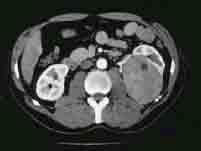

选项 A.B超常表现为不均质的中低回声实性肿块,但体积小的肾癌有时表现为高回声 B.IVU可见肾盏肾盂出现不规则变形、狭窄、拉长、移位或充盈缺损 C.CT对肾癌的确诊率不高,是目前诊断肾癌最可靠的影像学方法 D.肾错构瘤的脂肪成分表现为强回声,CT扫描呈负值,容易鉴别 E.B超、CT不能确诊的肾癌可作肾动脉造影检查

答案 C